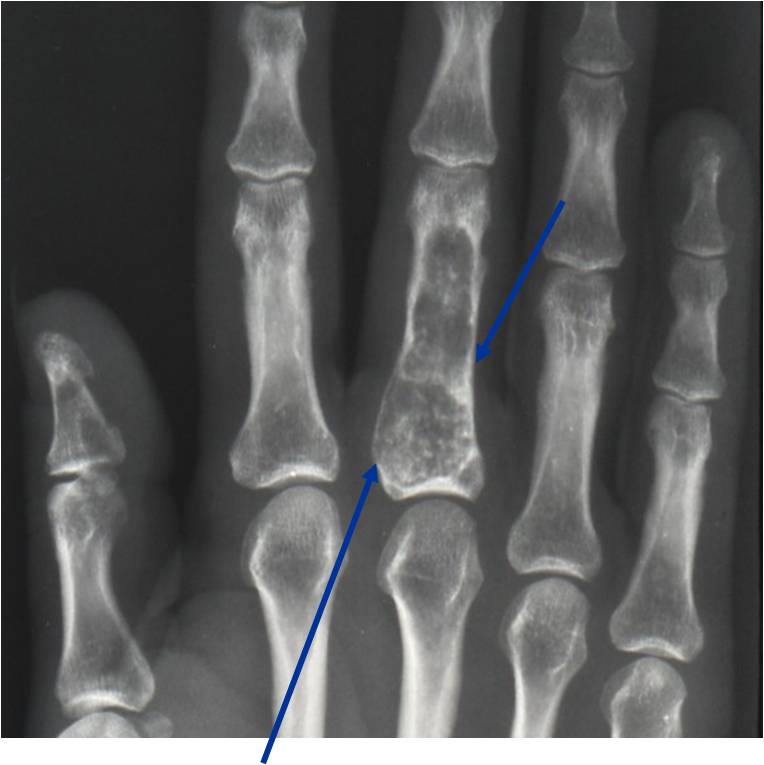

- Localized, radiolucent defect usually with punctate calcifications

- Cortex may be scalloped and thinned in the phalanges

- Geographic lytic lesion

- Central often metaphyseal in long bones

- Expansile remodeling with thinned cortex

- Chondroid matrix with calcifications in majority of tumors

- Digits: Impending or actual pathological fracture